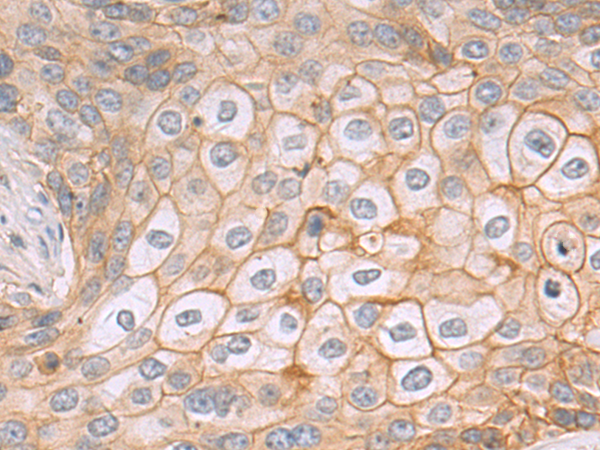

分类: 科研抗体货号: P08313别名: FAPA; SIMP; DPPIV; FAPalpha应用: WB,IHC反应种属: Human, Mouse